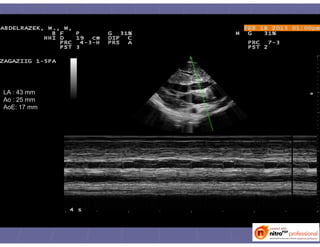

LA : 43 mm

Ao : 25 mm

AoE: 17 mm

RV DIAM d : 11.6 mm

IVS dia : 22.6 mm

LVD dia : 38.8 mm

PW dia : 21.3 mm

IVS sys : 26.5 mm

LVD sys : 25.9 mm

PW sys : 25.9 mm

EF : 63 %

FRACT SH : 33 %

SEP THICK : 17 %

PW THICK : 21 %

LV MASS : 516 g